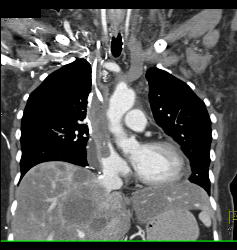

SVC Occlusion With Collaterals. SVC Occlusion Was Due to Tumor